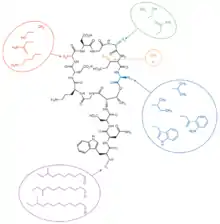

Biosynthesis

Daptomycin is a cyclic lipopeptide antibiotic produced by Streptomyces roseosporus.[30][31] Daptomycin consists of 13 amino acids, 10 of which are arranged in a cyclic fashion, and three on an exocyclic tail. Two nonproteinogenic amino acids exist in the drug, the unusual amino acid L-kynurenine (Kyn), only known to daptomycin, and L-3-methylglutamic acid (mGlu). The N-terminus of the exocyclic tryptophan residue is coupled to decanoic acid, a medium-chain (C10) fatty acid. Biosynthesis is initiated by the coupling of decanoic acid to the N-terminal tryptophan, followed by the coupling of the remaining amino acids by nonribosomal peptide synthetase (NRPS) mechanisms. Finally, a cyclization event occurs, which is catalyzed by a thioesterase enzyme, and subsequent release of the lipopeptide is granted.

The NRPS responsible for the synthesis of daptomycin is encoded by three overlapping genes, dptA, dptBC and dptD. The dptE and dptF genes, immediately upstream of dptA, are likely to be involved in the initiation of daptomycin biosynthesis by coupling decanoic acid to the N-terminal Trp.[32] These novel genes (dptE, dptF ) correspond to products that most likely work in conjunction with a unique condensation domain to acylate the first amino acid (tryptophan). These and other novel genes (dptI, dptJ) are believed to be involved in supplying the nonproteinogenic amino acids L-3-methylglutamic acid and Kyn; they are located next to the NRPS genes.[32]

The decanoic acid portion of daptomycin is synthesized by fatty acid synthase machinery (Figure 2). Post-translational modification of the apo-acyl carrier protein (ACP, thiolation, or T domain) by a phosphopantetheinyltransferase (PPTase) enzyme catalyzes the transfer of a flexible phosphopantetheine arm from coenzyme A to a conserved serine in the ACP domain through a phosphodiester linkage. The holo-ACP can provide a thiol on which the substrate and acyl chains are covalently bound during chain elongations. The two core catalytic domains are an acyltransferase (AT) and a ketosynthase (KS). The AT acts upon a malonyl-CoA substrate and transfers an acyl group to the thiol of the ACP domain. This net transthiolation is an energy-neutral step. Next, the acyl-S-ACP gets transthiolated to a conserved cysteine on the KS; the KS decarboxylates the downstream malonyl-S-ACP and forms a β-ketoacyl-S-ACP. This serves as the substrate for the next cycle of elongation. Before the next cycle begins, however, the β-keto group undergoes reduction to the corresponding alcohol catalyzed by a ketoreductase domain, followed by dehydration to the olefin catalyzed by a dehydratase domain, and finally reduction to the methylene catalyzed by an enoylreductase domain. Each KS catalytic cycle results in the net addition of two carbons. After three more iterations of elongation, a thioesterase enzyme catalyzes the hydrolysis, and thus release, of the free C-10 fatty acid.

To synthesize the peptide portion of daptomycin, the mechanism of an NRPS is employed. The biosynthetic machinery of an NRPS system is composed of multimodular enzymatic assembly lines that contain one module for each amino acid monomer incorporated.[33] Within each module are catalytic domains that carry out the elongation of the growing peptidyl chain. The growing peptide is covalently tethered to a thiolation domain; here it is termed the peptidyl carrier protein, as it carries the growing peptide from one catalytic domain to the next. Again, the apo-T domain must be primed to the holo-T domain by a PPTase, attaching a flexible phosphopantetheine arm to a conserved serine residue. An adenylation domain selects the amino acid monomer to be incorporated and activates the carboxylate with ATP to make the aminoacyl-AMP. Next, the A domain installs an aminoacyl group on the thiolate of the adjacent T domain. The condensation (C) domain catalyzes the peptide bond forming reaction, which elicits chain elongation. It joins an upstream peptidyl-S-T to the downstream aminoacyl-S-T (Figure 7). Chain elongation by one aminoacyl residue and chain translocation to the next T domain occurs in concert. The order of these domains is C-A-T. In some instances, an epimerization domain is necessary in those modules where L-amino acid monomers are to be incorporated and epimerized to D-amino acids. The domain organization in such modules is C-A-T-E.[33]

The first module has a three-domain C-A-T organization; these often occur in assembly lines that make N-acylated peptides.[33] The first C domain catalyzes N-acylation of the initiating amino acid (tryptophan) while it is installed on T. An adenylating enzyme (Ad) catalyzes the condensation of decanoic acid and the N-terminal tryptophan, which incorporates decanoic acid into the growing peptide (Figure 3). The genes responsible for this coupling event are dptE and dptF, which are located upstream of dptA, the first gene of the Daptomycin NRPS biosynthetic gene cluster. Once the coupling of decanoic acid to the N-terminal tryptophan residue occurs, the condensation of amino acids begins, catalyzed by the NRPS.

The first five modules of the NRPS are encoded by the dptA gene and catalyze the condensation of L-tryptophan, D-asparagine, L-aspartate, L-threonine, and glycine, respectively (Figure 4). Modules 6-11, which catalyze the condensation of L-ornithine, L-aspartate, D-alanine, L-aspartate, glycine, and D-serine are encoded for the dptBC gene (Figure 5). dptD catalyzes the incorporation of two nonproteinogenic amino acids, L-3-methylglutamic acid (mGlu) and Kyn, which is only known thus far to daptomycin, into the growing peptide (Figure 6).[31] Elongation by these NRPS modules ultimately leads to macrocyclization and release in which an α-amino group, namely threonine, acts as an internal nucleophile during cyclization to yield the 10-amino-acid ring (Figure 6). The termination module in the NRPS assembly line has a C-A-T-TE organization. The thioesterase domain catalyzes chain termination and release of the mature lipopeptide.[33]